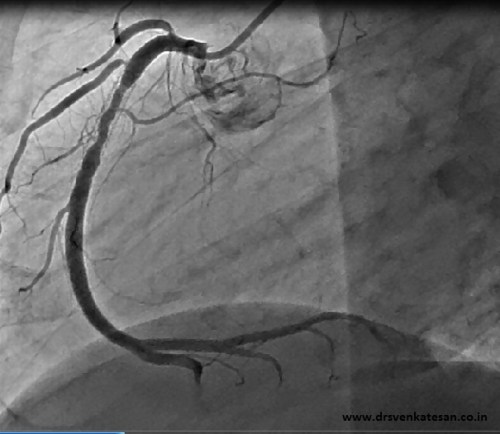

An in vitro heart with special catheters showing the true extent of coronary circulation: Courtesy http://eurheartj.oxfordjournals.org/content/28/3/278.full.pdf+html